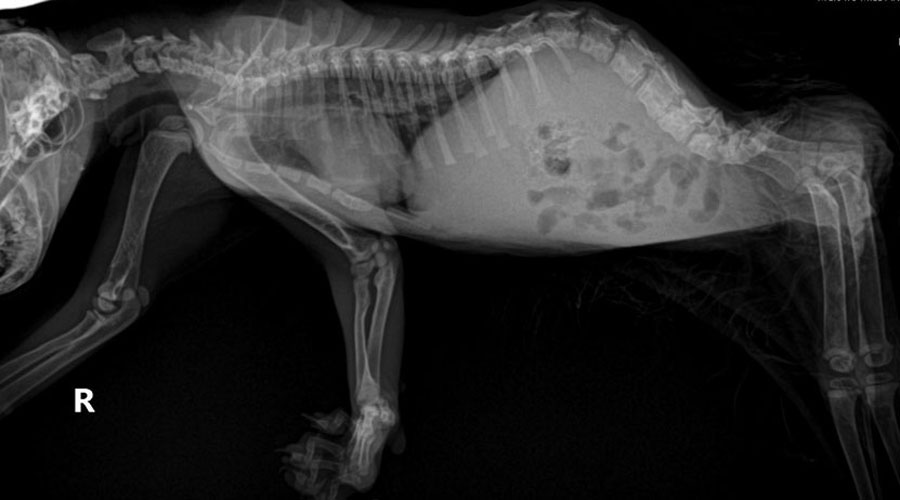

Flipper is a rumpy (tailless) paraplegic due to the birth defect spina bifida causing posterior deformities and rear limb atrophy.

Pedals has spinal damage of unknown origin causing posteriorly recumbent paraplegia and neurologic issues.

Cavallo has complete use of his legs, but a tail pull injury caused an acute spinal separation and the most severe elimination deficits of the three.